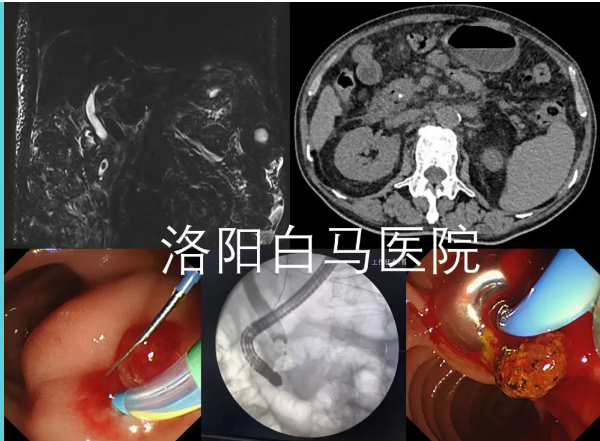

吕后宁主任首先为老人安排了上腹部CT检查。影像结果显示胆总管扩张,其末端可见高密度影,考虑结石可能。结合患者数年前曾有胆囊切除的病史,胆总管末端结石成为首要怀疑诊断。

为进一步明确结石的具体位置、大小,并排除其他可能引起梗阻性黄疸的病因(如胆管肿瘤、胆管狭窄等),随后为患者进行了MRCP检查。这项检查能更清晰地显示胆道系统的全貌。MRCP结果清晰证实了胆总管下端存在充盈缺损,即结石嵌顿,从而明确了胆总管末端结石”的诊断。这一严谨的步骤确保了诊断的准确性,为制定精准的治疗方案奠定了基础。

经全面检查评估,洛阳白马医院消化内科陈宏伟主任与吕后宁主任共同认为,采用经内镜逆行胰胆管造影(ERCP)取石术是适合该患者的优选方案。此项技术通过自然腔道(经口-胃-十二指肠)进行操作,体表无切口,具有创伤小、痛苦轻、恢复快的突出特点,对患者全身生理机能干扰较小,尤其有助于高龄患者平稳度过围手术期。

在充分的术前准备后,由陈宏伟主任与吕后宁主任共同为患者施行了ERCP取石术。术中,通过内镜精准定位,顺利将胆总管末端的结石取出,解除了胆道梗阻。